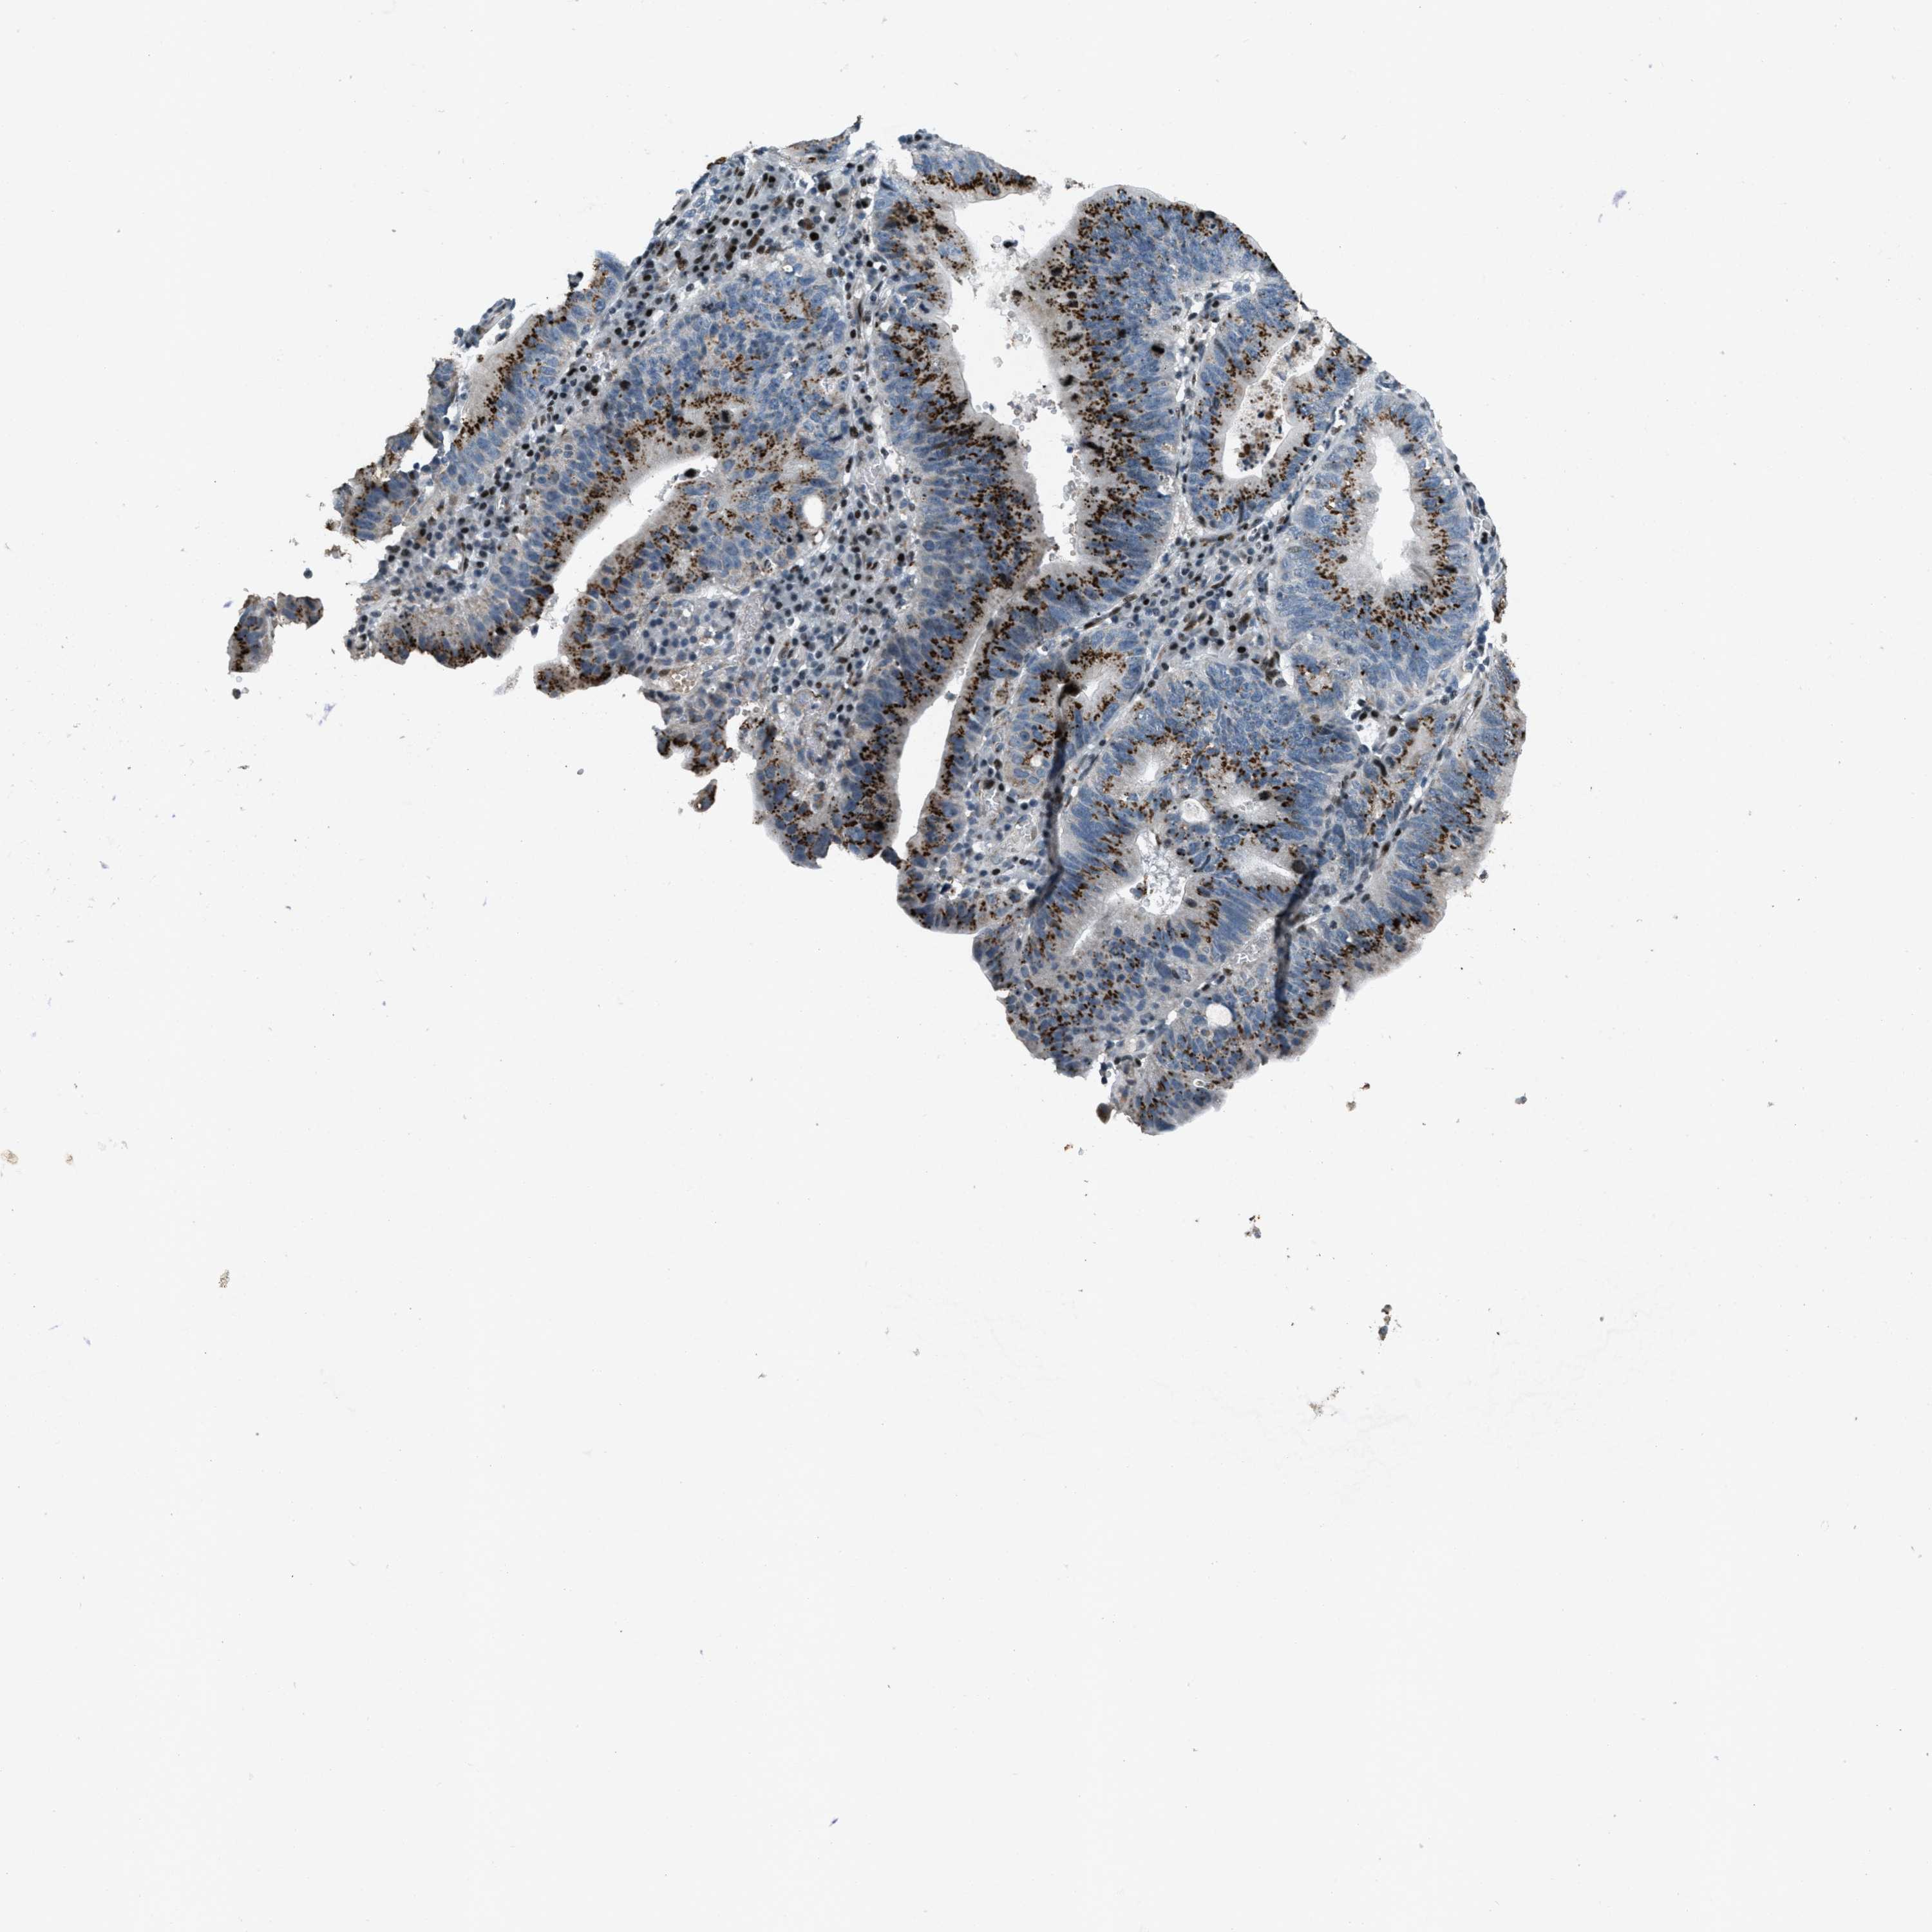

STOMACH CANCER - Protein expressioni

A mouse-over function shows sample information and annotation data. Click on an image to view it in a full screen mode. Samples can be filtered based on level of antibody staining by selecting one or several of the following categories: high, medium, low and not detected. The assay and annotation is described here.

Note that samples used for immunohistochemistry by the Human Protein Atlas do not correspond to samples in the TCGA dataset.

Antibody stainingi

Antibody staining in the annotated cell types in the current human tissue is reported as not detected, low, medium, or high, based on conventional immunohistochemistry profiling in selected tissues. This score is based on the combination of the staining intensity and fraction of stained cells.

Each image is clickable and will lead to virtual microscopy that enables deeper exploration of all samples and also displays staining intensity scores, fraction scores and subcellular localization as well as patient and tissue information for each sample.

Antibody HPA017671

Staining

High

Medium

Low

Not detected

Intensity

Strong

Moderate

Weak

Negative

Quantity

>75%

75%-25%

<25%

None

Location

Nuclear

Cytoplasmic/membranous

Cytoplasmic/membranous,nuclear

Adenocarcinoma, NOS